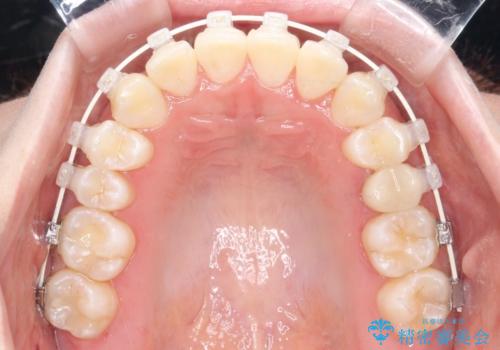

- インビザライン、ワイヤー矯正

- 前歯のガタツキが気になるとのことで来院されました。

ワイヤー矯正とインビザライン矯正を併用することによって、治療期間の短縮と、より良い仕上がりを目指す治療を選択することとしました。

インビザライン(アライナー)矯正とワイヤー矯正のそれぞれの利点を生かした治療を行い、綺麗な歯並びになりました。